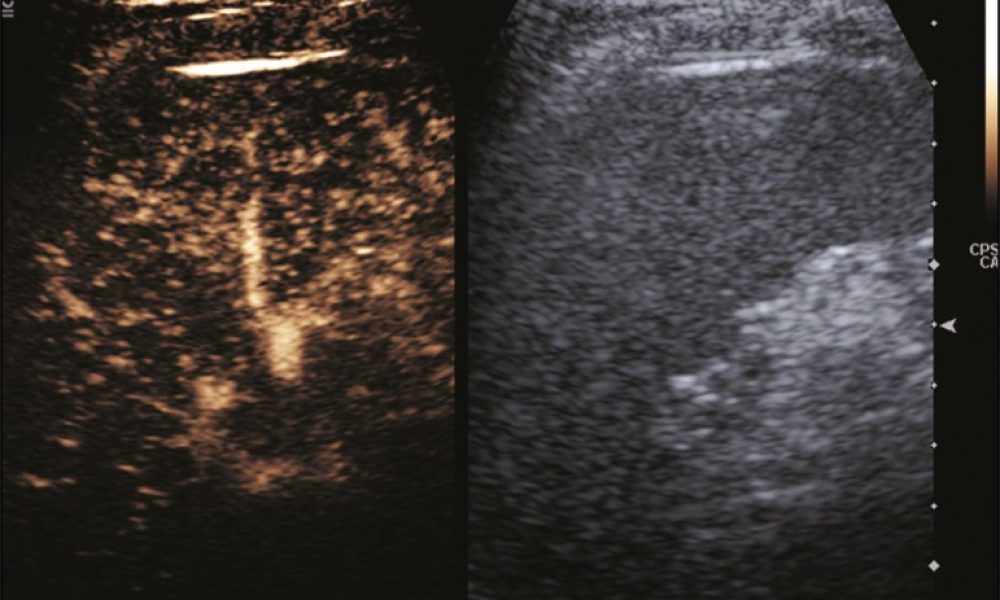

A caracterização de lesões focais esplênicas pela ultrassonografia pode ser bastante desafiadora. A introdução da ultrassonografia com contraste por microbolhas vem ganhando papel importante no campo da avaliação por imagem das doenças esplênicas, oferecendo um método livre de radiação ionizante. Após a implementação da ultrassonografia contrastada na prática médica, doenças malignas como linfomas e metástases, bem como benignas, como cistos, lesões traumáticas e hemangiomas, podem ser observadas e caracterizadas de maneira acurada, sem a necessidade de prosseguir a investigação com outros métodos de imagem. Mais especificamente, lesões traumáticas esplênicas podem ser acompanhadas por meio da ultrassonografia contrastada, evitando a radiação ionizante da tomografia computadorizada, uma vez que as fraturas esplênicas e suas potenciais complicações são seguramente demonstradas por esse método ultrassonográfico. Na nova era do uso dos contrastes para ultrassonografia, mais pacientes serão beneficiados por investigações livres de radiação para avaliação de afecções do baço, com alta acurácia diagnóstica.